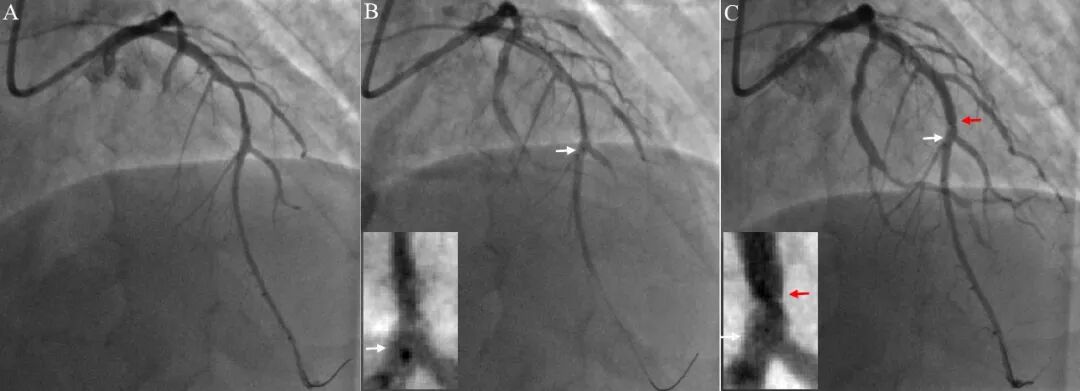

图6 支架张力性移位(长病变)。前降支中段长病变(A)。支架初始位置过远达至前降支远段,回拉支架,远端定位良好(B, 白色箭头为支架远端位置,齐平对角支发出处)。支架释放时向近端跳跃(C,白色箭头为支架原定位处,红色箭头为支架实际释放处)。